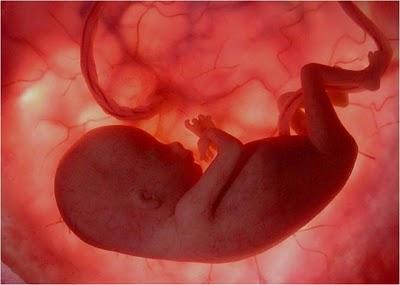

Las imágenes utilizadas en esta presentación son parte del documental "En el vientre materno" producido por National Geographic.

Son imágenes obtenidas a través de una micro-cámara introducida en el útero de una gestante. Gracias a las modernas técnicas fotográficas es posible acompañar el fascinante proceso de gestación de un bebé.

UN EMBRIÓN DE POCAS SEMANAS QUE SE ENCUENTRA EN EL INTERIOR DEL ÚTERO DE SU MADRE.

ESTÁ EN EL INICIO DE SU DESARROLLO.

ES APENAS EL PRINCIPIO DE UN SER HUMANO Y EN ESTE ESTADO PODRÍA SER CONFUNDIDO CON EL EMBRIÓN DE UN MACACO.

JUNTO A ÉL SE ENCUENTRA EL SACO VITELINO,PROPORCIONÁNDOLE LOS NUTRIENTES QUE NECESITAEN LAS PRIMERAS SEMANAS DE VIDA.

ALREDEDOR DE LA 8ª SEMANA DE GESTACIÓN EL SACO VITELINO PIERDE SUS FUNCIONES. EL CORDÓN UMBILICAL EMPEZARÁ AALIMENTARLO CON NUTRIENTES TOMADOS DELCUERPO MATERNO A TRAVÉS DE LA PLACENTA.

MIENTRAS TODO ESTO SUCEDE, ÉL FLOTA TRANQUILAMENTE,EN EL ÚTERO DE SU MADRE.